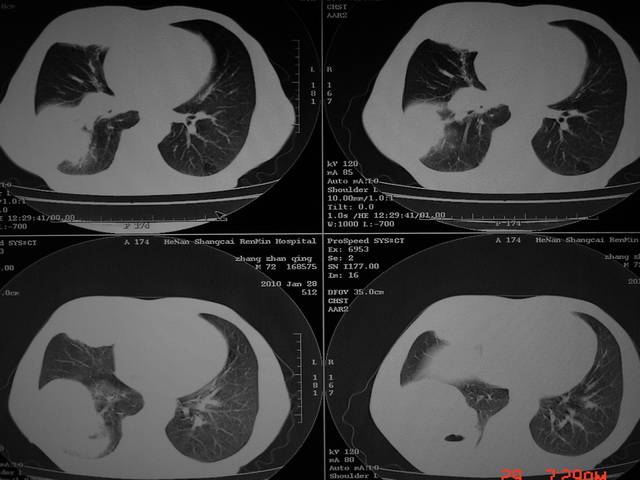

标题: CT24386:M 72岁农民 右侧胸痛6月余,咳嗽,无发热、咯血等 [打印本页]

xx m 72岁农民 右侧胸痛6月余,咳嗽,无发热、咯血等

右下周围型肺癌,并右肺门、纵膈淋巴结、内乳淋巴结转移,右胸膜转移累及前胸壁。鉴别:脓肿、tb、淋巴瘤。病理类型可能为大细胞型。

这个病人有点复杂了,上纵隔像是占位,右肺下叶见壁光整厚壁空洞加液平,像是肺脓肿,中叶病灶牵涉到胸膜及胸壁,形态看像是炎性病变,总之不能除外恶性病变,还是穿刺或增强后再说。

右下周围型肺癌。偏心空洞形成伴感染。

右下周围型肺癌伴转移

支持2搂,考虑右肺下叶周围性肺癌伴肺门及纵膈淋巴结转移!右侧前纵膈病灶,还是一元论考虑为胸壁或胸膜转移瘤。

右侧周围性肺癌,胸膜转移。

支持 右肺下叶周围型肺癌并右肺门、纵膈淋巴结、内乳淋巴结转移,右胸膜转移累及前胸壁。